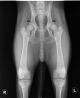

Jámborházi Kedves Nemély, MET.Ku.47/14

Kan 2014 - Hári Endre Miklós